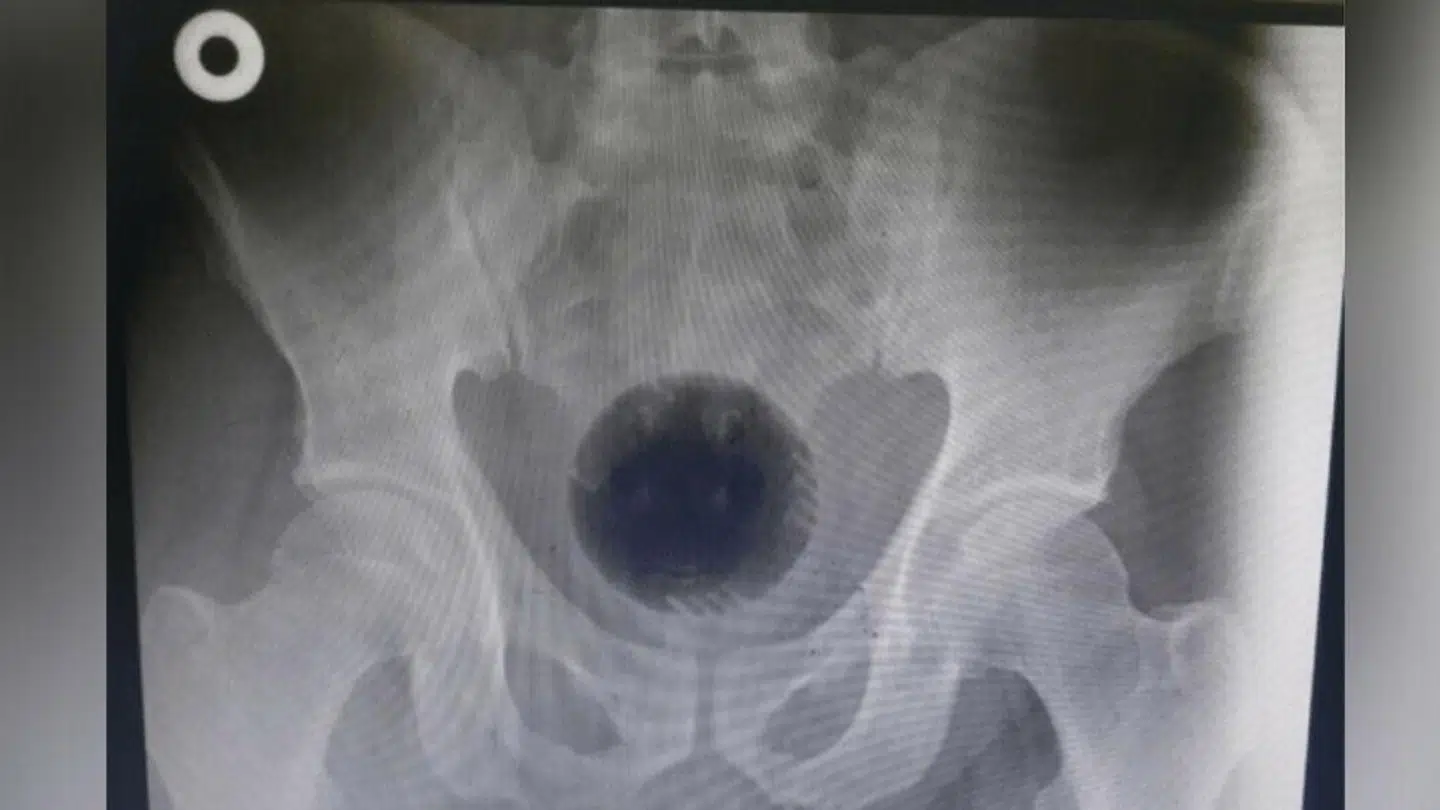

Derfor tog lægerne røntgenbilleder af mandens underliv for at vurdere situationen. Det førte til, at den 51-årige blev forsøgt opereret den følgende morgen.